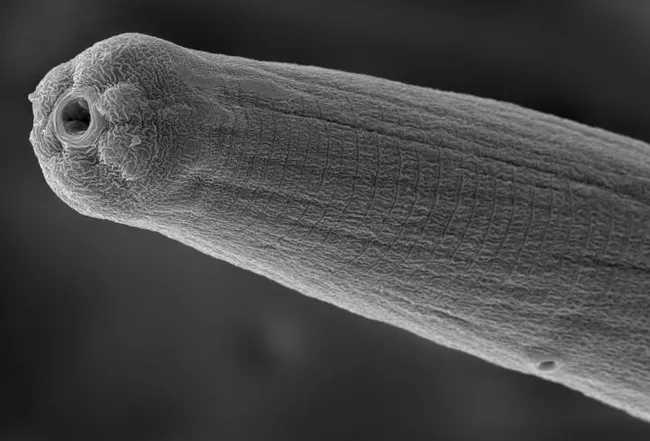

Who knew that you, along with billions of other people, could be infected with undetected microscopic parasitic nematodes, or round worms? And that they spit venom?

"Parasitic nematodes are master manipulators of host immunity," Dillman says in his abstract. "Little is known about the identity and function of the cocktail of effectors they release during active infection. We have developed an effector discovery model using entomopathogenic nematodes and fruit flies, which we are using to identify and characterize potent modulators of insect immunity."

Dillman, who joined the UC Riverside faculty in February 2015 and is now an associate professor, focuses his research on identifying the specific proteins in a nematode's spit or venom that can trick the immune system to ignore its presence. His model organism is the fruit fly. He hopes that his research could lead to treatments for autoimmune diseases in humans, such as celiac, Crohn's or inflammatory bowel diseases.

"You can have a person riddled with infection who never realized there's a 2-centimeter-long worm in their eye and thousands of parasites in their blood," Dlllman told her. "The immune system never signaled something was wrong. How is that possible? We know very little about how that works."

Devastating Parasites. Nematodes, he says, are "devastating parasites of humans, capable of modulating our biology in numerous ways, including suppressing our immune systems. The goal of my lab is to understand this modulation and to characterize the chemical pathways that allow it to happen. There's compelling data that parasites could even be used to treat autoimmune disorders such as Crohn's or inflammatory bowel disease. Parasitic worms are just the coolest things you could study because there are so many strange interactions, both positive and negative, that occur between the worms and their hosts."